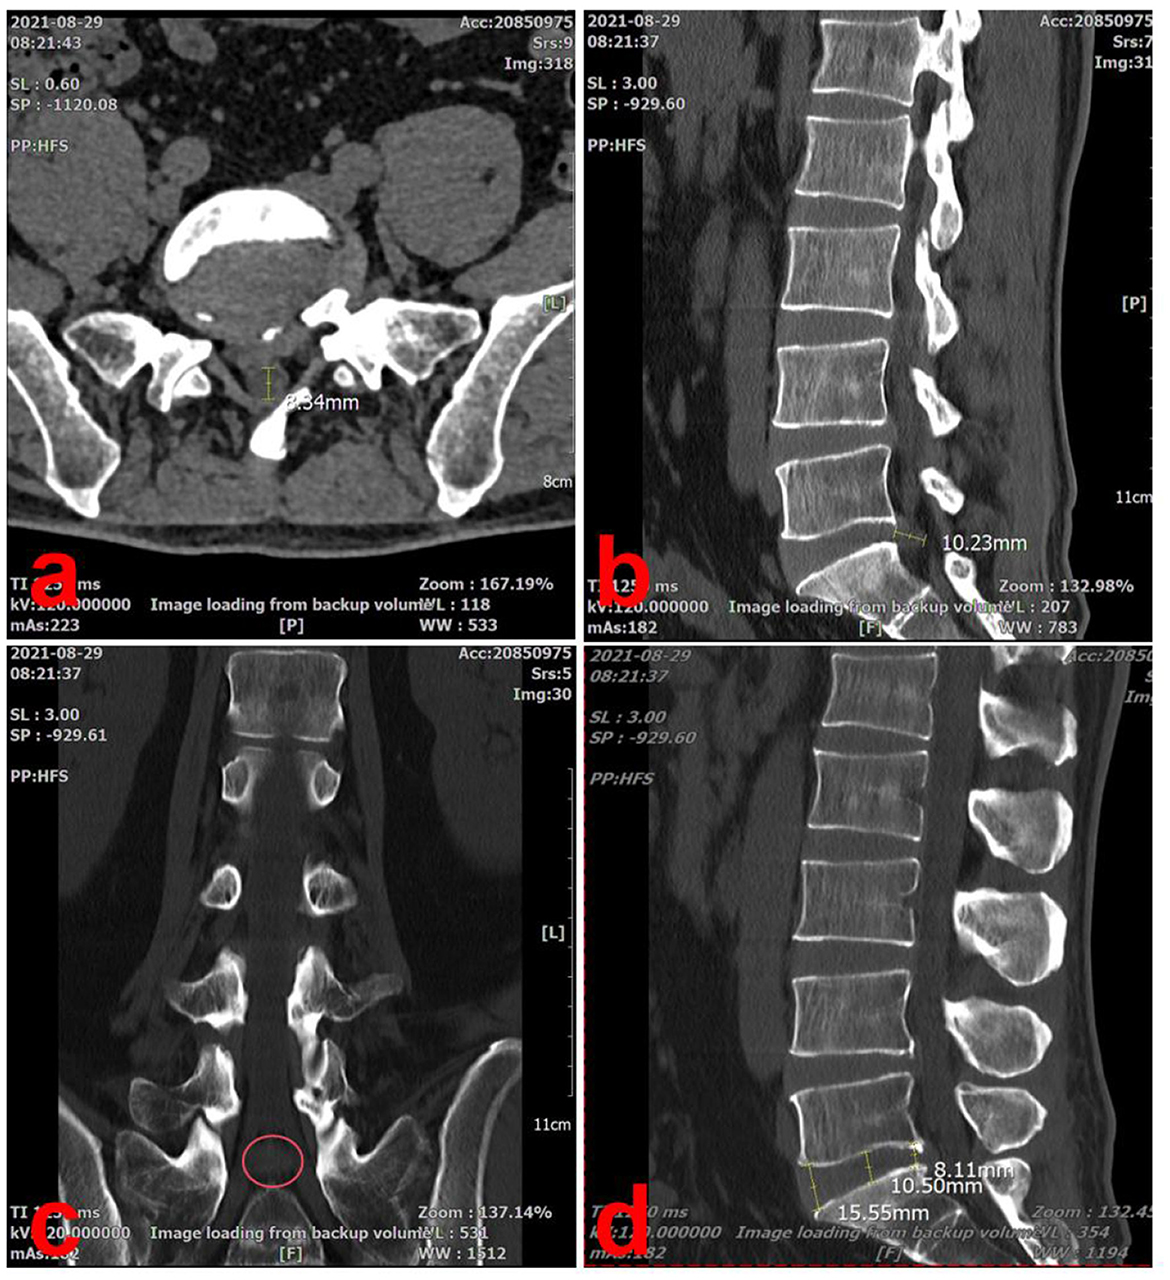

A computed tomography (CT) scan showed a large right-sided disc herniation at the L5/S1 level, with an Michigan State University (MSU) classification of 3-AB (15) (Figure 2a). On the sagittal view of the L5/S1 intervertebral space, the herniated disc measured 10.23 mm in length and the height of the lumbar intervertebral space was 11.83 mm (Dabbs method: the height of the front + posterior edge/2) (Figures 2b, d). On the cross-section view, the diameter of the spinal canal at the L5/S1 level was 8.34 mm (Figure 2a). The coronal view, the herniated disc was compressing the right S1 nerve root, consistent with the patient's symptoms (Figure 2c).

Figure 2

CT scan images of a spine, labeled a to d. Image a shows an axial view of the pelvis with a measurement of 34.4 millimeters. Image b focuses on a sagittal view of the lumbar spine with a measurement of 10.23 millimeters. Image c displays a coronal view of the lumbar region with a red circle highlighting an area. Image d presents a lateral view of the lumbar spine with measurements of 8.11 millimeters, 10.50 millimeters, and 15.55 millimeters.

Figure 2. Lumbar spine CT scan at the initial visit (2021-08-29). (a) On the cross-section view, the diameter of the spinal canal at the L5/S1 level was 8.34 mm. (b) On the sagittal view of the L5/S1 intervertebral space, the herniated disc measured 10.23 mm in length. (c) The coronal view, the herniated disc was compressing the right S1 nerve root, consistent with the patient's symptoms (red circle). (d) On the sagittal view, the height of the lumbar intervertebral space was 11.83 mm.